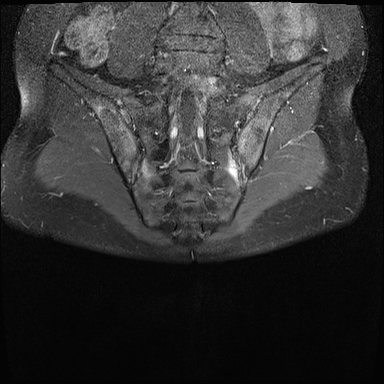

X-quang

Xơ cứng dưới sụn và bào mòn hai bên khớp cùng chậu do viêm khớp cùng chậu.

MRI

MRI chuỗi xung T1W sau tiêm thuốc tương phản từ của cùng bệnh nhân cho thấy bờ khớp cùng chậu không đều do bào mòn.

Có ngấm thuốc ở xương dưới sụn và phù nề tủy xương.

Không có tràn dịch khớp.

Thuốc tương phản từ tiêm tĩnh mạch không nhất thiết phải sử dụng để chẩn đoán viêm khớp cùng chậu.

Cuộn qua các hình ảnh MRI và so sánh với các dấu hiệu trên X-quang (hình ảnh cuối cùng).

Chẩn đoán phân biệt viêm khớp cùng chậu:

- Thoái hóa khớp: xơ cứng dưới sụn hai bên khớp cùng chậu không kèm bào mòn.

- Viêm xương đặc xương chậu (Osteitis condensans ilii): xơ cứng hình tam giác hai bên ở xương chậu tiếp giáp với khớp cùng chậu.

Chẩn đoán viêm khớp cùng chậu có thể gặp khó khăn khi chỉ dựa vào X-quang. Việc bổ sung X-quang cột sống thắt lưng hoặc các phương tiện chẩn đoán khác có thể giúp tăng độ chắc chắn trong chẩn đoán.